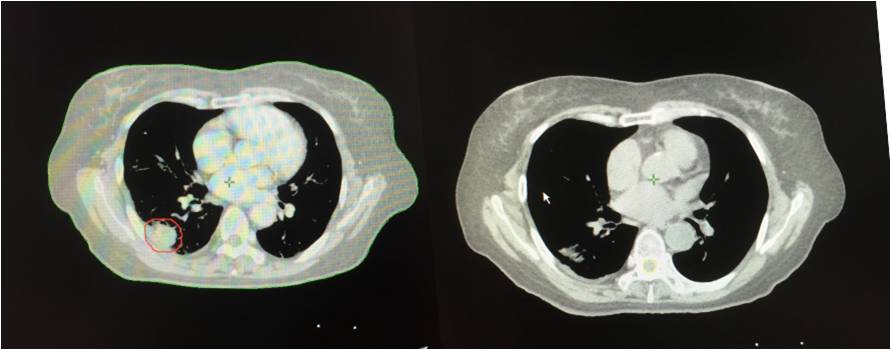

治疗前 治疗后

2013年3月初无明显诱因出现胸闷、气短,活动时加重,伴有间断左侧肩胛区疼痛,无咳嗽、咳痰,无发热、咯血,无盗汗、乏力。2013年4月胸部CT示:右肺占位。4月末在北京大学人民医院行胸部CT增强示:双肺下叶背段恶性病变,考虑肺癌可能性大。5月在*警武**北京总队第二医院行PET/CT检查提示:1.双肺下叶背段斜裂胸膜下高代谢结节,考虑恶性病变,肺癌可能大,双肺多发磨玻璃结节及微小结节,未见明显高代谢,倾向恶性病变;2.右乳外下象限小结节伴代谢,结合临床。

2013年5月入院,肺穿刺病理结果提示:左下肺腺癌。

2013年5月、6月接受四次A45肿瘤治疗治疗四次。2013年10月再次接受全身A45肿瘤治疗1次,右下肺病灶A45肿瘤治疗1次,出院后继续口服易瑞沙靶向治疗。患者肿瘤缩小,几乎消失。患者的态势稳定。